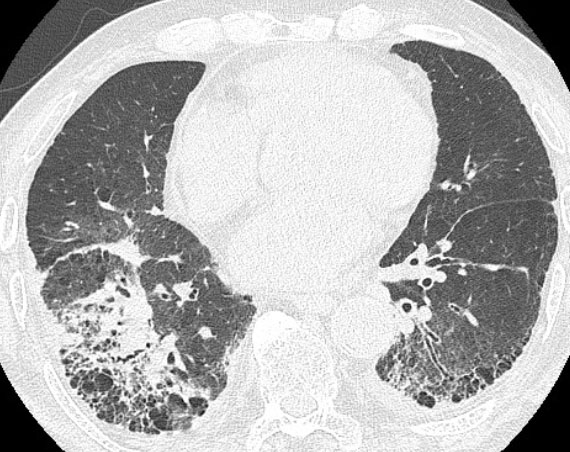

In a routine follow-up visit one and three months after end of repeat SBRT, she had no symptoms. Five months later, the patient visited the emergency room with dyspnea. Chest CT showed diffuse bilateral ground-glass opacity with interlobular septal thickening (Figure 3). High-dose methylprednisolone and empirical antibiotics were initiated for a diagnosis of radiation pneumonitis and/or pulmonary infection. Unfortunately, she failed to improve and died six months after the end of repeat SBRT. She was diagnosed with grade 5 radiation pneumonitis, which was considered to be the main cause of death.

Figure 3: Chest CT showed diffuse bilateral ground-glass opacity with interlobular septal thickening.